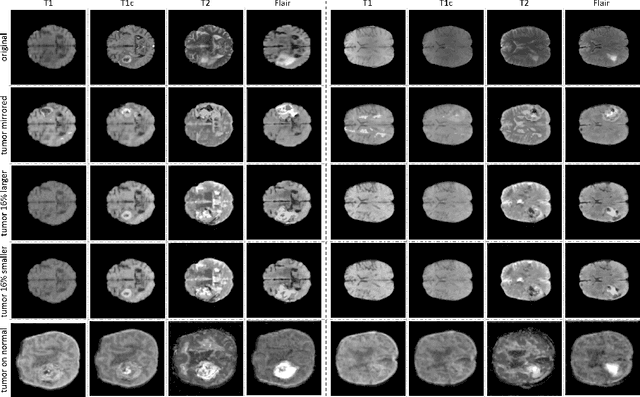

Data diversity is critical to success when training deep learning models. Medical imaging data sets are often imbalanced as pathologic findings are generally rare, which introduces significant challenges when training deep learning models. In this work, we propose a method to generate synthetic abnormal MRI images with brain tumors by training a generative adversarial network using two publicly available data sets of brain MRI. We demonstrate two unique benefits that the synthetic images provide. First, we illustrate improved performance on tumor segmentation by leveraging the synthetic images as a form of data augmentation. Second, we demonstrate the value of generative models as an anonymization tool, achieving comparable tumor segmentation results when trained on the synthetic data versus when trained on real subject data. Together, these results offer a potential solution to two of the largest challenges facing machine learning in medical imaging, namely the small incidence of pathological findings, and the restrictions around sharing of patient data.